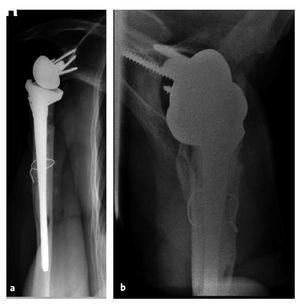

Figuras 10a y 10b. a) Mujer de 63 años con placa de osteosÃntesis en el húmero proximal para fijar una fractura conminuta colocada en otro centro en agosto de 2002. b) Revisión a hemiartroplastia (Neer II) en septiembre de 2002 en otro hospital para resolver una luxación de la placa y malalineación persistente de los fragmentos de la fractura. El paciente se presentó en nuestras consultas externas en septiembre de 2003. La puntuación de la Escala de Constant era de 16 con dolor y limitación de la movilidad (flexión 70º, abducción 70º). La hemiartroplastia habrÃa migrado anterosuperiormente debido a la insuficiencia del manguito de los rotadores. El paciente fue ingresado para cirugÃa de revisión protésica del hombro.

Figuras 11a y 11b. RadiografÃas del hombro derecho (a: AP, b: proyección axial) 25 meses tras la cirugÃa. Se colocó una prótesis invertida de vástago largo. Ventana ósea quirúrgica fijada con un cerclaje alámbrico.

Figuras 12a a 12d. Movilidad a los 25 meses de la operación. Flexión activa 140º y abducción 100º. Existe un déficit residual evidente en la rotación externa activa con el brazo en abducción. La puntuación del Constant mejoró hasta 58,6 puntos (83,7% ponderado por edad). La paciente no tenÃa dolor y estaba muy satisfecha con el resultado quirúrgico.